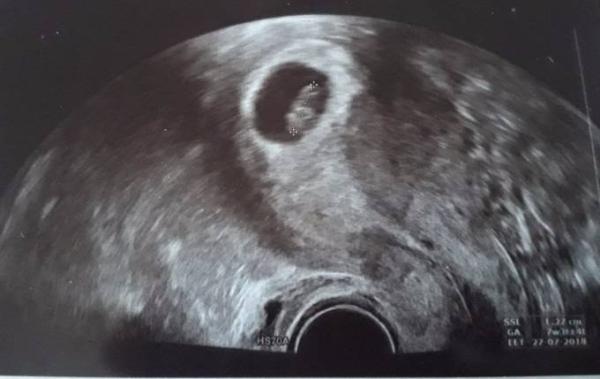

Das Herchen schlägt und es ist alles gut.. Statt den 24.7.18 hat er mich nun auf den 27.7.18 datiert.